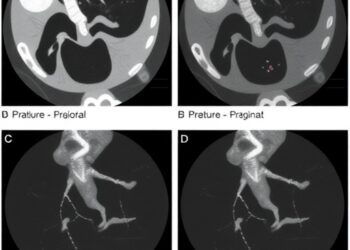

Endoscopic Retrograde Cholangiopancreatography in Pediatric Bile Duct Cases

In a groundbreaking study, researchers from a single medical center have spotlighted the effectiveness of endoscopic retrograde cholangiopancreatography (ERCP) in ...